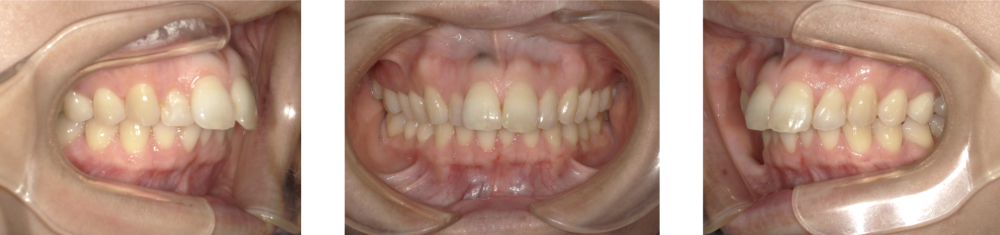

ガミースマイル中等度症例画像

中等度(歯茎が3〜5mm程度見える)方の場合

笑ったときの写真を見ると歯茎がはっきり写っていたり、人前で笑うときに「口元が気になる…」と意識し始めている状態が、中等度のガミースマイルのイメージです。

このレベルになると、

• 矯正治療で前歯の位置を少し歯茎側へ下げる

• 咬み合わせの高さやバランスを整える

• 歯茎のラインや歯の長さのバランスも一緒にととのえるる

といったように、「歯の位置・咬み合わせ・歯茎の見え方」をセットで考えた治療が必要になります。 場合によっては、アンカースクリューを使って前歯の動きをより細かくコントロールすることもあります。治療期間の目安は歯並びにもよりますが、1年〜1年半ほどかけて、少しずつ丁寧に整えていくことが多いです。